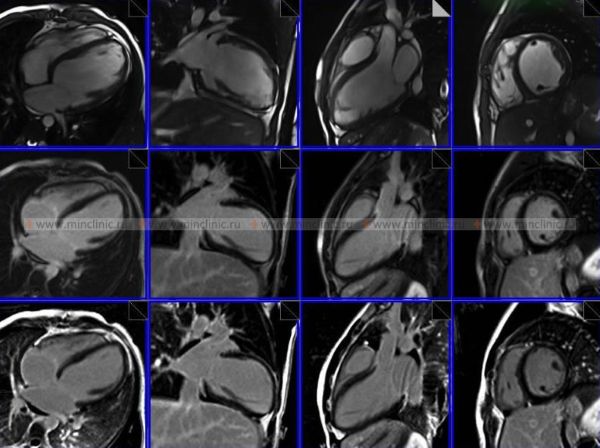

МРТ (магнитно-резонансная томография) органов грудной клетки — это способ визуализации с применением силового магнита и радиоволн, с помощью которых в дальнейшем строится изображение органов грудной клетки (сосуды, сердце, лёгкие). Во время проведения МРТ (магнитно-резонансной томографии) органов грудной клетки 3,0 Т (тесла) пациент не получает радиационного облучения (лучевой нагрузки).

МРТ (магнитно-резонансная томография) грудной клетки позволяет специалистам получить изображение расположенных там органов пациента (сердце, бронхи, лёгкие и т.д.) для оценки их функционального состояния или выявить произошедшие в них органические изменения.

- оценка органов грудной клетки в трёхмерной реконструкции под разными углами;

МРТ (магнитно-резонансной томографии) органов грудной клетки может показать следующие нарушения в сердце, лёгких или грудной клетке:

- ишемическая кардиомиопатия;

- рестриктивная кардиомиопатия;